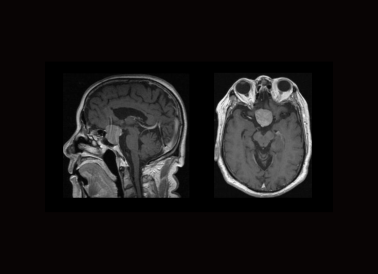

´Å¹²Õñ¼¹ÖùË®³ÉÏñ¡¢Ñª¹Ü³ÉÏñ¡¢µ¨µÀ¼°ÃÚÄòϵˮ³ÉÏñ£»ÈéÏÙ¶¯Ì¬ÔöÇ¿£»ÃÖÉ¢¼ÓȨ³ÉÏñ£»´ÅÃô¸Ð¼ÓȨ³ÉÏñ£»´Å¹²ÕñHÖÊ×ÓÆµÆ×ÆÊÎö£»ÄÔ¶¯Ì¬ÔöÇ¿

ÖÐÊàÉñ¾¹Ç÷ÀµÄMRIºÍCTµÄÓ°ÏñÕï¶Ï£¬ÒÔ¼°PET/CTÆÀ¼ÛÖ×ÁöÁÆÐ§£¬ÕÒÔ·¢ÐÔÖ×ÁöµÈ